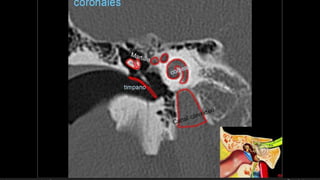

Evaluación Imagenologica

• #51 IZQ: Canal arqueado(petromastoideo) . Canal SC superior DER: Hiato del facial(blanca), ganglio geniculado (negra)